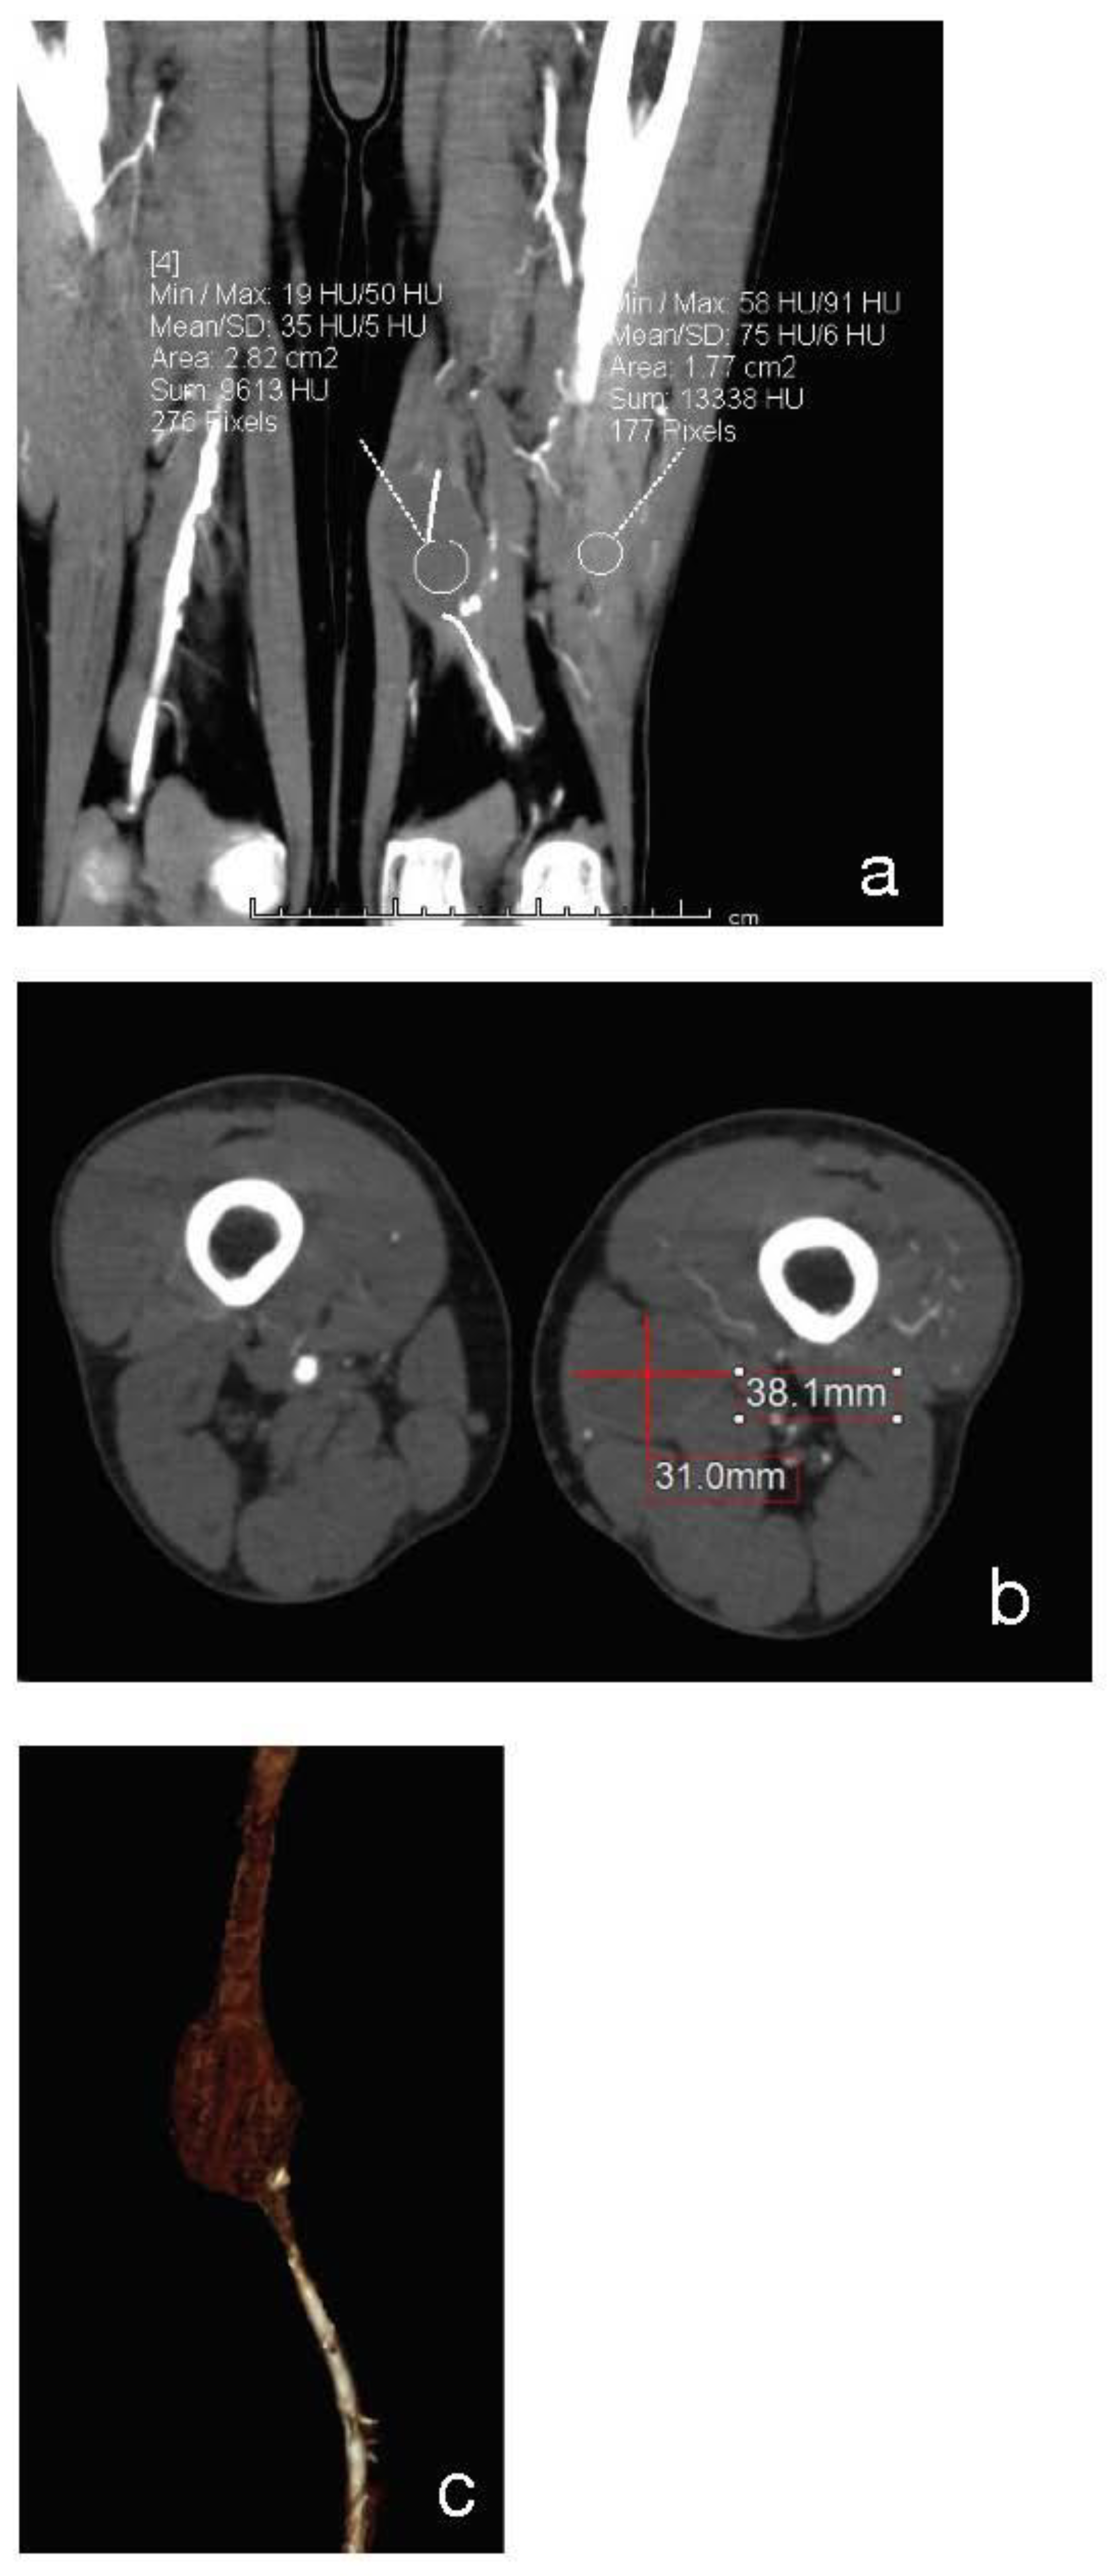

Figure 2. Coronal (a), Axial (b) and 3D-reconstruction (c) show the occlusion of distal anastomotic PA.

On clinical examination, he had leg pain and swelling. There was no presence of motor or sensory deficits. Rutherford classification Grade II, Category 4, with AP < 38 mmHg. The angio-CT scan of the abdomen and lower limbs revealed that the iliac artery, common femoral artery and deep femoral artery of the left side were atheromasic but patent, whereas the FP bypass was completely occluded (Figure 1). At distal anastomosis, a PA which measured 31 × 38 × 55 mm was present (Figure 2a–c). The left popliteal artery was revascularized by collateral vessels coming from the deep femoral artery. On the right side, there was regular patency of the leg arteries.